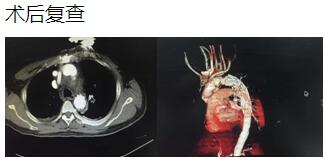

心胸外科成功完成一例淺低溫停循環(huán)下行主動(dòng)脈夾層手術(shù)

通訊員 李小升 報(bào)道:近日,衡陽市中心醫(yī)院心胸外科成功完成一例淺低溫停循環(huán)下“孫氏手術(shù)”(升主動(dòng)脈置換、主動(dòng)脈弓置換、降主動(dòng)脈術(shù)中支架置入)。

患者是一位48歲中年男性,因胸痛1小時(shí)入院,我院CT提示主動(dòng)脈夾層累及胸、腹主動(dòng)脈全層,診斷為主動(dòng)脈夾層(D ebaKey I型)。患者病情危重,手術(shù)治療是挽救其生命的唯一希望。為了挽救病人生命,經(jīng)過麻醉科、手術(shù)室、體外循環(huán)組的術(shù)前充分討論,心胸外科廖金文主任、廖承輝副主任帶領(lǐng)團(tuán)隊(duì)決定為其施行復(fù)雜而高難度的淺低溫停循環(huán)下“孫氏手術(shù)”。術(shù)中見主動(dòng)脈全程及三分支受累,右冠受累,冠脈開口受壓狹窄,予以行“升主動(dòng)脈 主動(dòng)脈弓置換 降主動(dòng)脈術(shù)中支架置入術(shù)”,團(tuán)隊(duì)成員歷經(jīng)約10個(gè)小時(shí)的奮戰(zhàn),手術(shù)順利完成。術(shù)后六小時(shí)患者意識(shí)完全清醒,現(xiàn)在已完全康復(fù)。